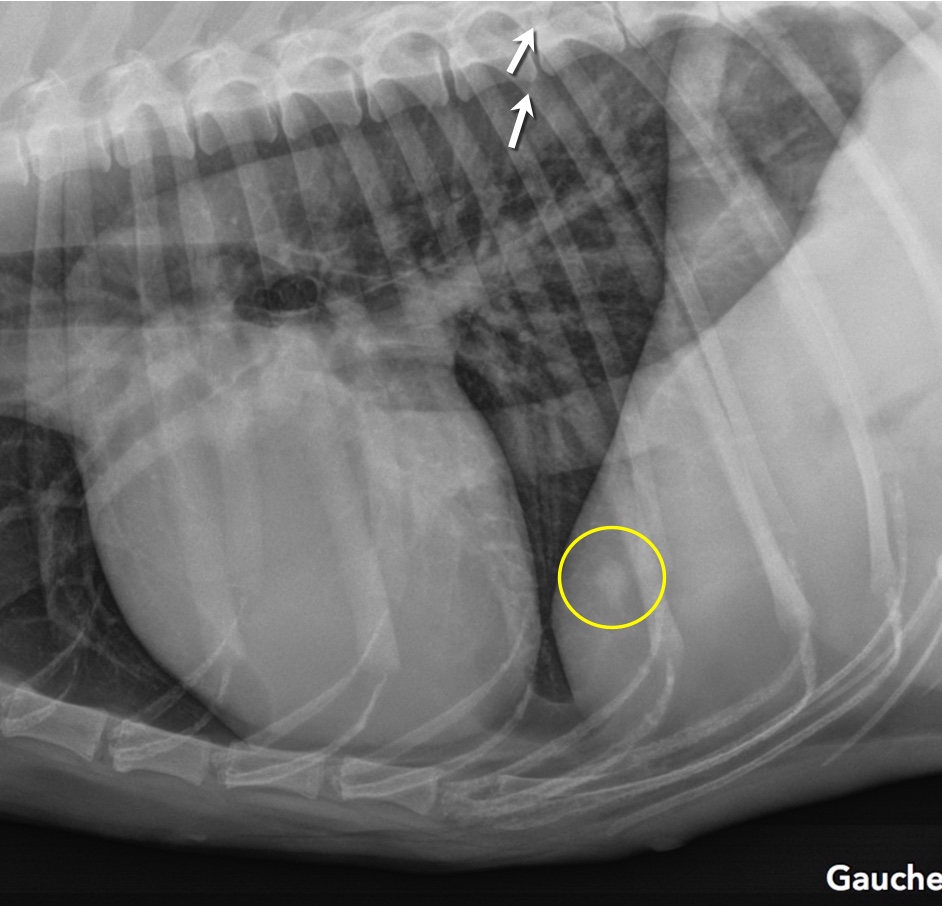

Latérale gauche initiale